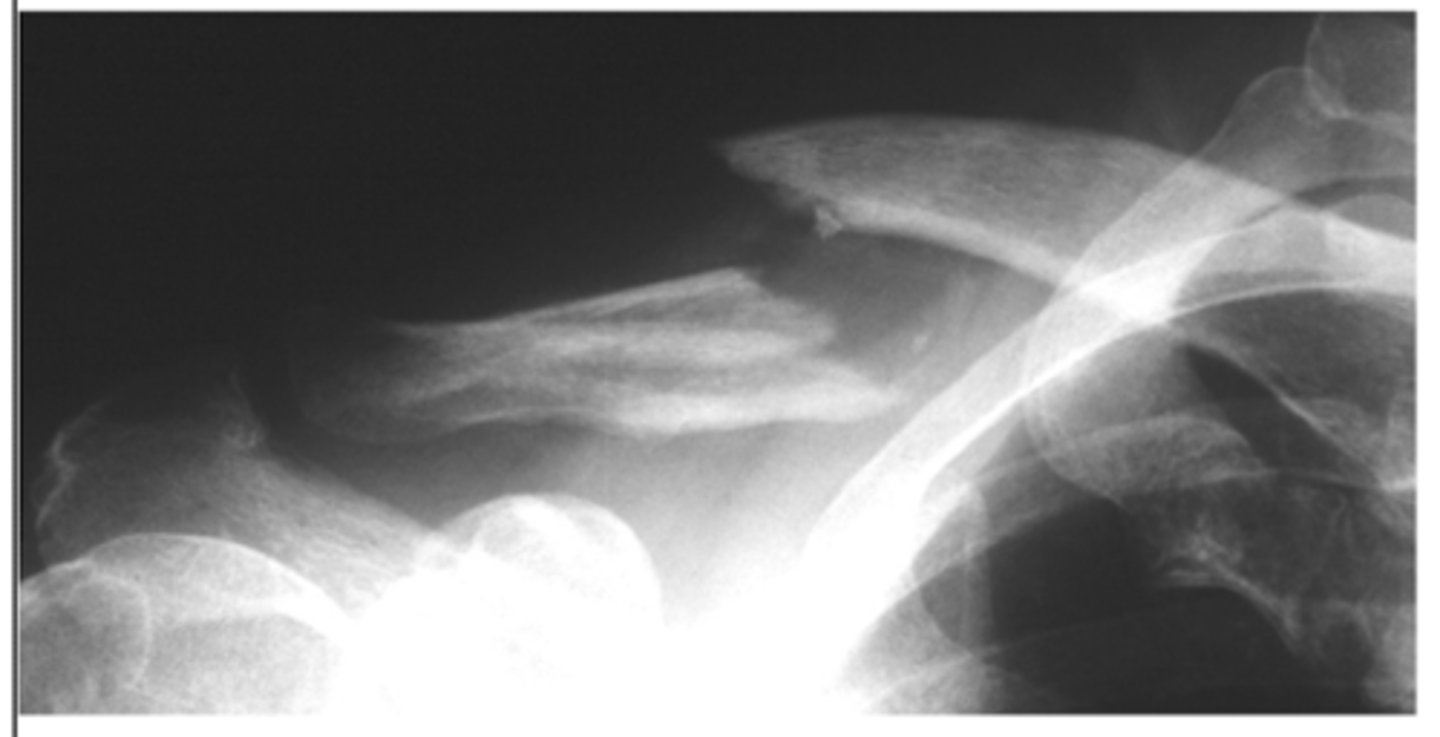

Where is a clavicle fracture most common?

middle 1/3

What on PE can suggest a clavicle fracture?

bump or tent deformity

shoulder droop

What TWO XR views can confirm a clavicle fracture?

AP view

10 degrees cephalic tilt

What is the most common treatment for a clavicle fracture?

non-surgical

- immobilization

- NSAIDs